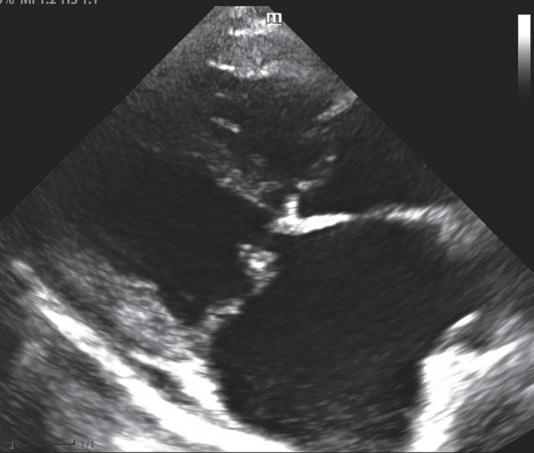

regurgitación tricuspídea en modo bidimensional y en modo M

El estudio y evaluación de la válvula tricúspide debe hacerse desde cortes paraesternales derechos (eje largo y corto) y desde cortes apicales izquierdos optimizados. La observación de lesiones valvulares mixomatosas o de prolapso valvular indican la existencia de patología (figura 1). La observación de cambios en las cavidades derechas, como hipertrofia excéntrica o concéntrica del ventrículo derecho, aumento del volumen del atrio derecho o dilatación del tronco pulmonar, también serían indicativos de insuficiencia valvular asociada a patología, luego no fisiológica.